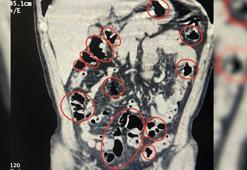

Midelerinde uyuşturucu taşıyan şüpheliler adliyede

Midelerinde uyuşturucu taşıyan şüpheliler adliyedeKayseri'de midelerinde metamfetamin ile yakalanan 2 şüpheli ile polisin bir başka uyuşturucu operasyonunda gözaltına alınan 4 kişi, emniyetteki işlemlerinin ardından adliyeye sevk edildi.